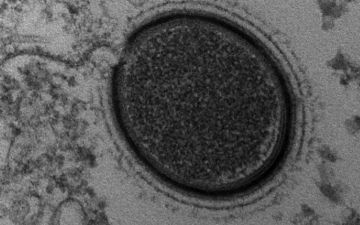

Во льдах обнаружили новые вирусы и бактерии — неужели новая опасность?